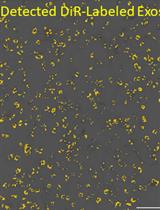

Graphical overview of extracellular vesicle (EV) isolation from plasma samples. (A) Flowchart of the isolation of extracellular vesicles from plasma, detailing plasma preparation and EV purification. (B) Transmission electron microscopy (TEM) image of EVs isolated from human plasma samples. Scale bar, 100 nm.